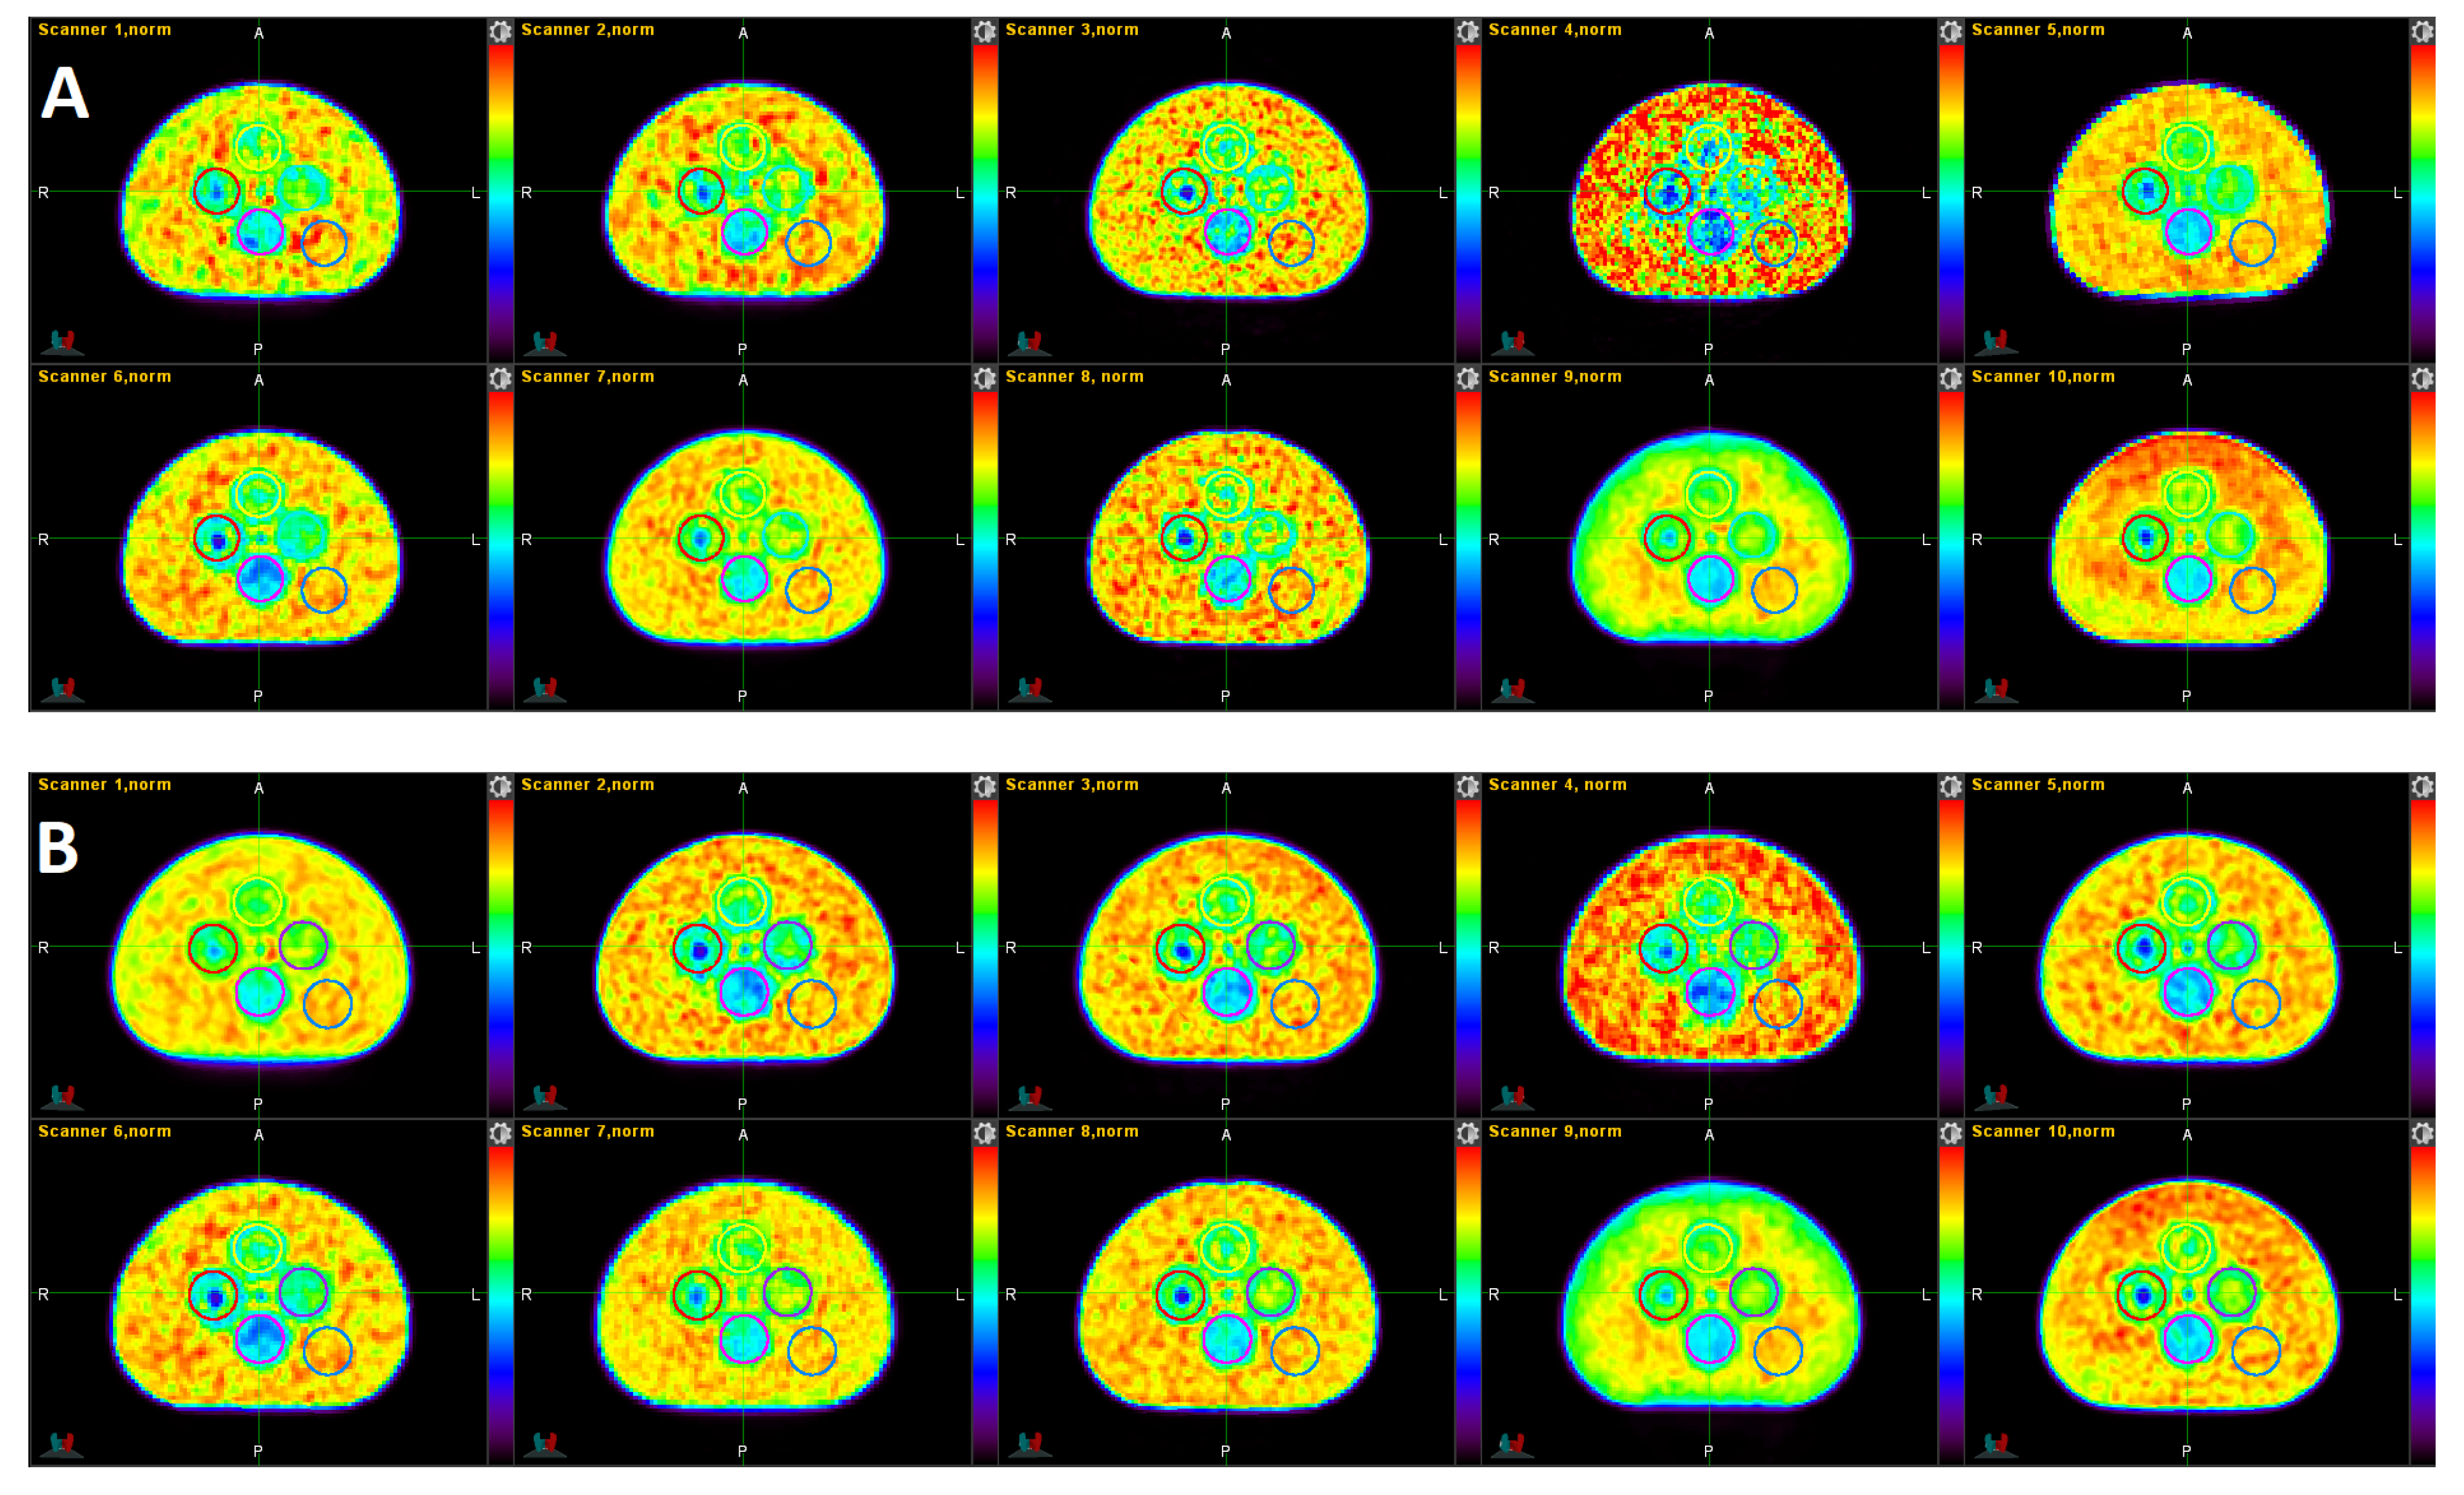

3.1. Qualitative Comparison